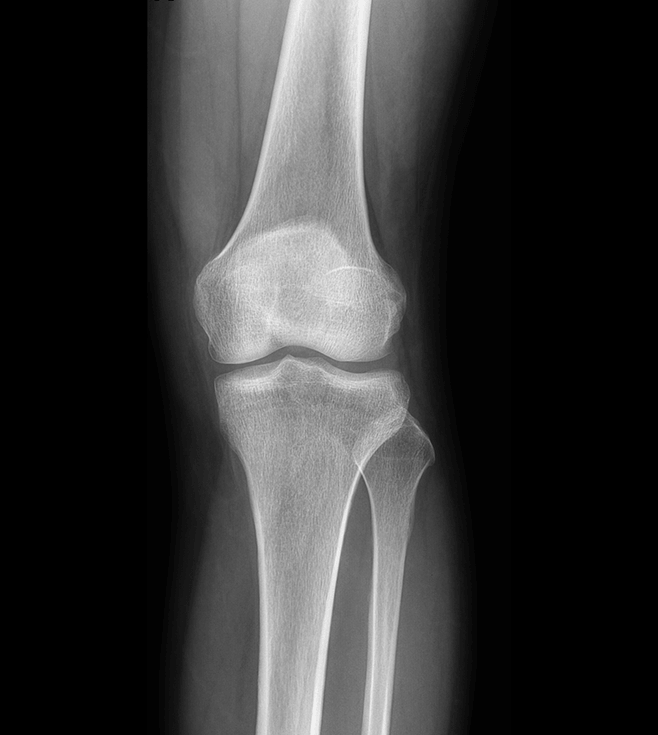

高清動態平板探測器

搭載自主研發超清大視野動態平板探測器,600微米碘化銫大幅提升X線轉化效率,獨特的非晶硅陣列與高速讀取集成電路緊密協作,輕松實現多幀率透視與高清點片。

17x17英寸

大幅面成像 -

900萬

高清像素點片 -

線性探測平面

圖像無畸變、無失真

專業的影像處理系統

“騰靈”系列搭載的IEAE影像處理系統,具備多項發明專利。本系統采用多頻域圖像處理技術,其6大核心處理模塊使影像具有優秀的一致性、柔和性、空間層次感和紋理細膩度,為用戶精準診斷病灶奠定了堅實的基礎。